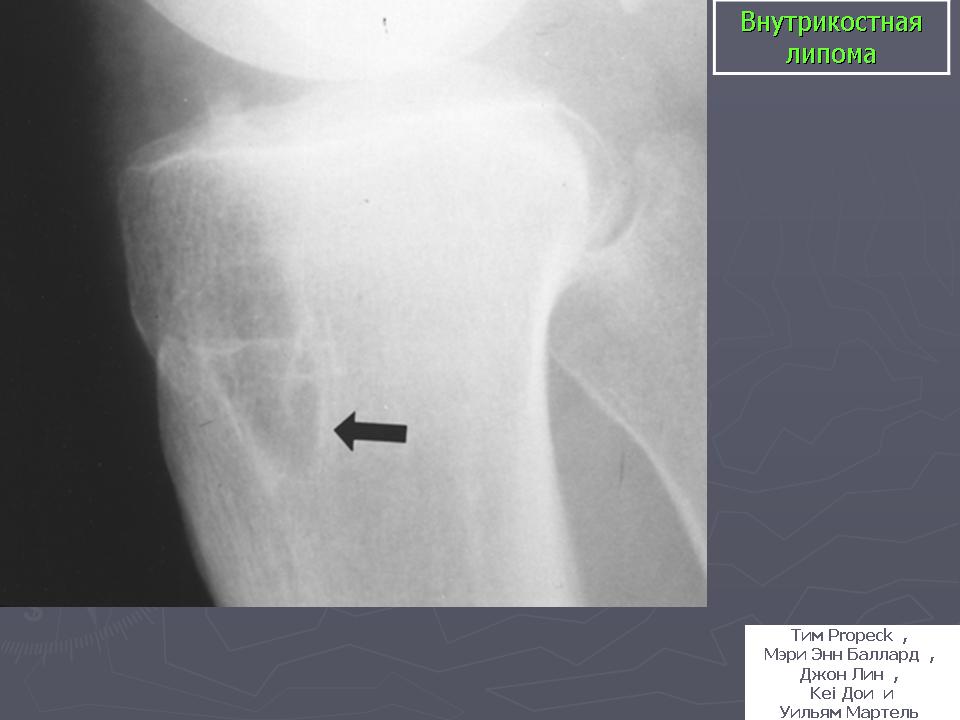

Липома

С Радиопедии.